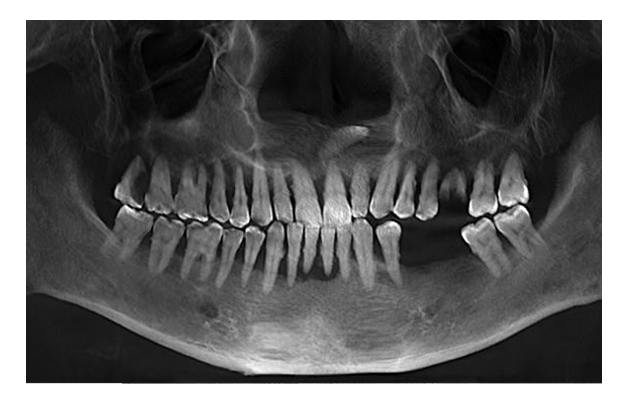

The latest Cone Beam CT Scanner: to assist our doctors in accurate diagnosis and coming up with treatment plan

Nobel Clinician software: to help our doctors determine the most suitable position for implant placement